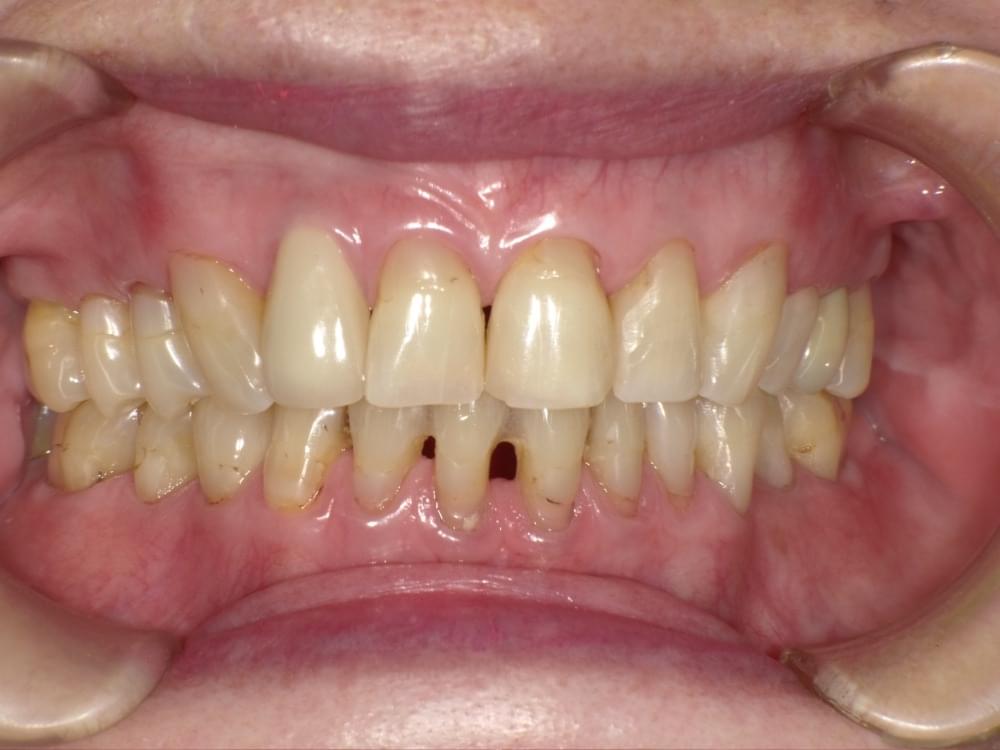

歯周病治療プログラムの治療例2

歯ぐきが下がってきた理由が分かりました!

歯ぐき下がりとかぶせ物の関係

治療の概要

治療内容

精密検査→歯周病治療プログラム→セラミック治療

※歯周病治療プログラムは行動科学に基づき、「自分の歯は自分で守る」という意識改革や行動変容を促しながら、スケーリングや歯ブラシ・フロス指導を行いました。

治療期間・回数・時間

6ヶ月・18回・計18時間

費用

精密検査 18,000円+税

歯周病治療プログラム 29,500円+税

セラミック治療(95,000円+税)×6本

リスク・副作用

歯肉の痛み・出血